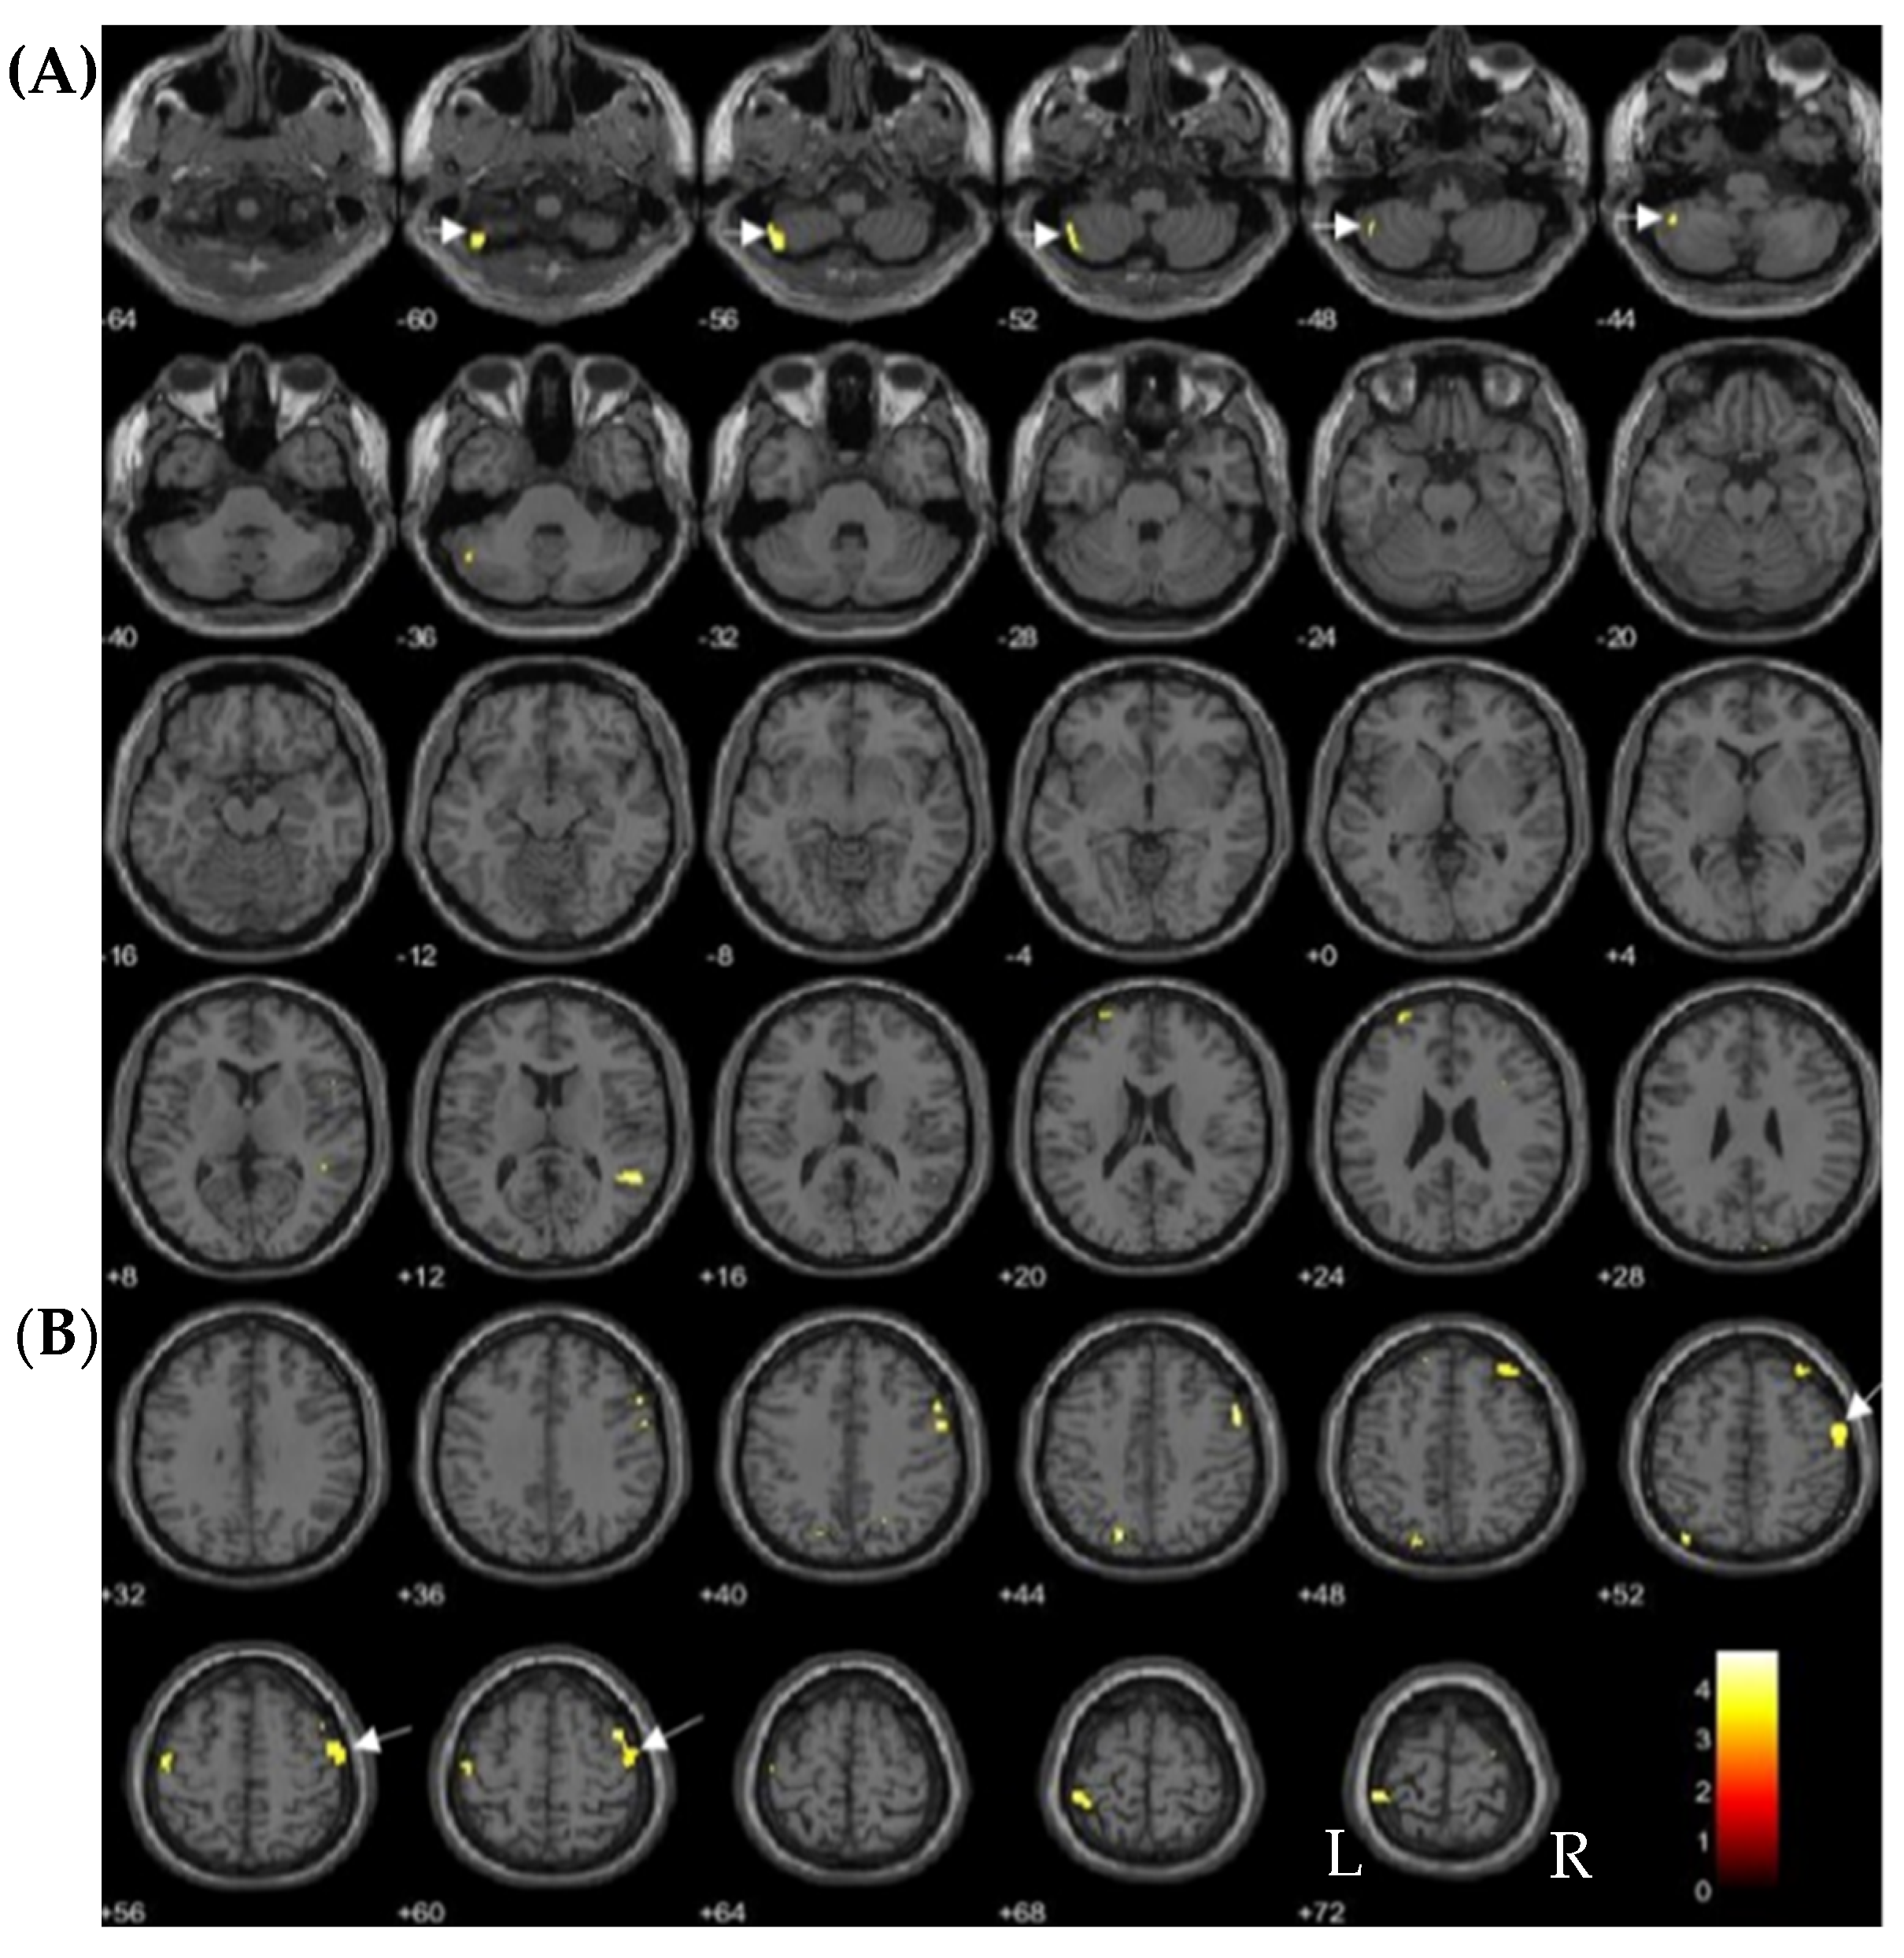

| Brain Regions | No of Voxels in Each Cluster (k) | Peak Z Scores | MNI Coordinates | ||

|---|---|---|---|---|---|

| x | y | z | |||

| Without exposure > With exposure | |||||

| Left inferior frontal gyrus pars orbitalis | 414 | 3.86 | −32 | 39 | −23 |

| With exposure > Without exposure | |||||

| No brain region | - | - | - | - | - |